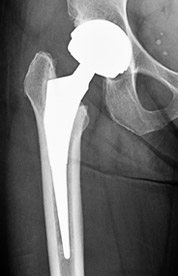

Ριζική θεραπεία αποτελεί η ολική αρθροπλαστική του ισχίου, δηλαδή ολική αντικατάσταση της άρθρωσης με προθέματα. Η επέμβαση ξεκίνησε προ 50 ετών και έδωσε λύση σε εκατομμύρια ασθενών που μέχρι τότε ήταν λειτουργικά ανάπηροι.